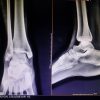

Case Report: We present a case of a 65-year-old male farmer who presented with swelling and persistent pain in the right foot, particularly over the third toe. The patient had a history of trivial trauma and previous incision and drainage for a foot swelling. Radiographic and magnetic resonance imaging findings indicated a well-defined lytic lesion with cortical thinning and breach over the third metatarsal, raising suspicion for tuberculous osteomyelitis. Surgical exploration revealed an encapsulated cyst filled with cheesy material. No sequestrated bone or osteomyelitis was found.

A 65-year-old male farmer presented to the outpatient department with complaints of swelling and persistent pain in the right foot, particularly over the third toe. The patient had been experiencing localized swelling and pain for the past 4–6 weeks, which did not subside despite treatment with antibiotics and analgesics prescribed by his local practitioner. The patient, a farmer by profession, lives with his spouse in a rural setting. His occupation, which involves significant physical activity, including walking, standing, and heavy lifting, likely contributed to the stress on his feet. He has no significant history of smoking or alcohol use. The patient reported a prior history of minor trauma to the right foot 5 years ago, which was managed conservatively with no long-term complications. Two years ago, the patient experienced similar swelling in the same foot, for which an incision and drainage procedure was performed at an outside hospital. Still, there were no subsequent issues after the procedure. At the time of presentation, the patient denied any systemic symptoms such as fever, weight loss, or malaise. He also reported no history of chronic conditions like diabetes, hypertension, or autoimmune disorders. The patient was not taking any long-term medications except for those prescribed for pain and swelling during the current episode. He had no prior history of significant illnesses or surgeries other than the previous minor trauma and surgical intervention on his right foot (Fig. 1-7).